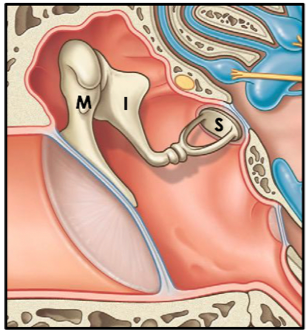

The ear is divided into 3 portions. What are they?

- External

- Middle

- Inner

a) external ear

b) middle ear

c) inner ear?

a) receives sound waves

b) transmits sound waves into mechanical waves

c) transmits sound waves into electrical waves